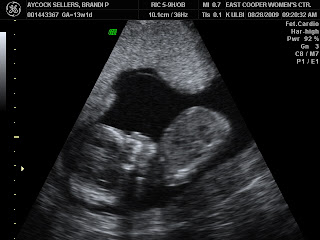

So today I went in for my first trimester screening and ultrasound. Our doctor recommended the screening based on some family history, not because anything is high risk :) The ultrasound piece looked great and we get the results from the blood test next Friday. Here are a few ultrasound photos for your viewing pleasure:

So we got confirmation last Friday that we are indeed 12 weeks pregnant! Tomorrow we will be 13 weeks and are excited to be finished with the first trimester. I've been really lucky that I haven't had too bad of a first trimester. I had a few days of nausea around my birthday but that was it, although I have been SUPER tired. Justin has been great about helping out while I've been too tired to do most anything, even helping with laundry! Our EDD (estimated delivery date) is March 4, so the little bean might have to share a birthday with a cousin if it decides to come early or late. We should find out sometime mid October whether it's a boy or girl and will definitely keep you posted. Here's an ultrasound photo for all those far away!